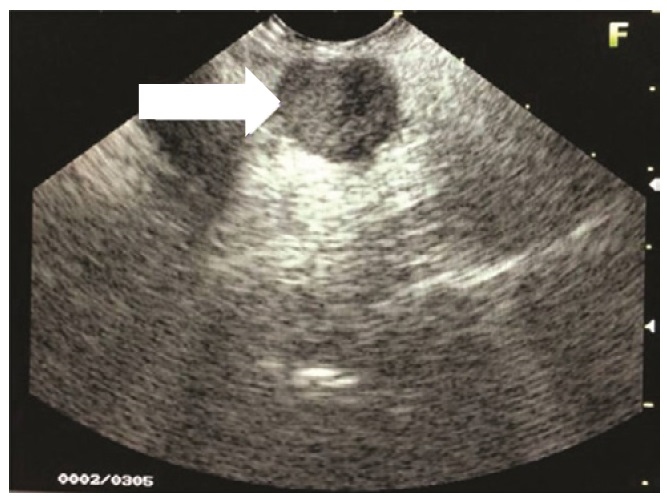

Endoscopic ultrasound revealed a 1.5 x 2.0 cm hypoechoic to isoechoic mass at the head of the pancreas (Figure 1). No increased vascularity was noted. There were no peripheral lymphadenopathies. The liver was free of any metastasis but appeared diffusely hyperechoic.

Click here to download Table 1Figure 1. Endoscopic ultrasound shows a 1.5 x 2.0 cm hypoechoic to isoechoic mass at the head of the pancreas.